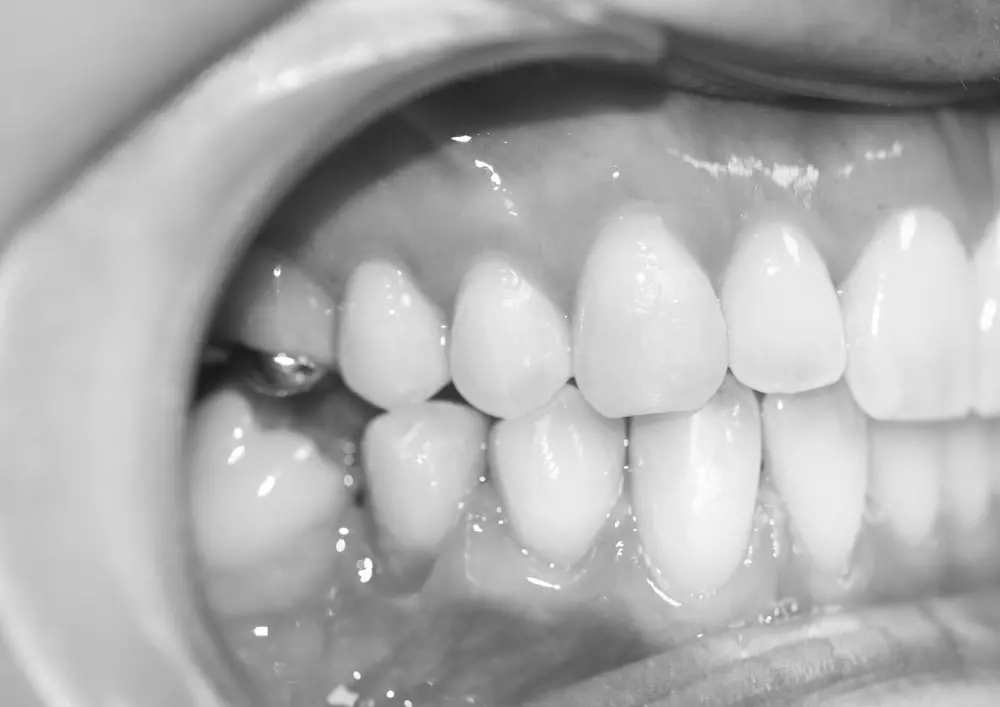

Licówki ceramiczne dają możliwość zachowania o ok. 40% więcej tkanki zęba w porównaniu do preparacji pod korony. Powoduje to zmniejszenie ryzyka wystąpienia powikłań endodontycznych. Użyteczność licówek ceramicznych w estetycznej rehabilitacji uśmiechu opisuje lek. dent. Adam Romaniuk-Demonchaux.